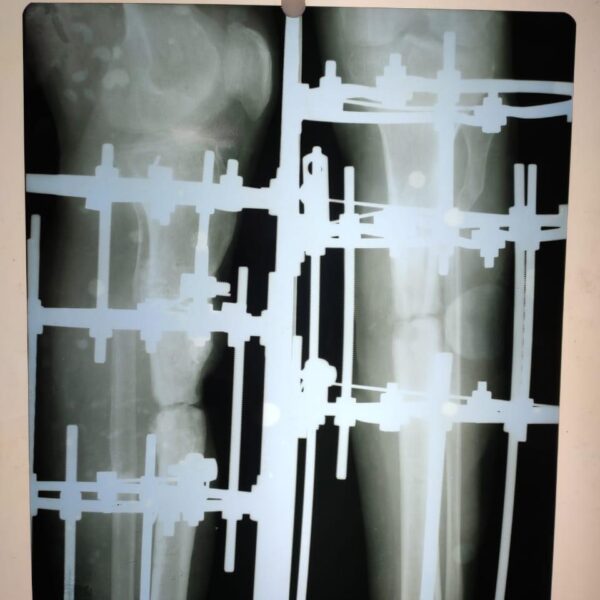

Moments That Mark Meaningful Recovery

Witness real patient transformations at The Ortho Clinic through images that reflect successful treatments and restored mobility.